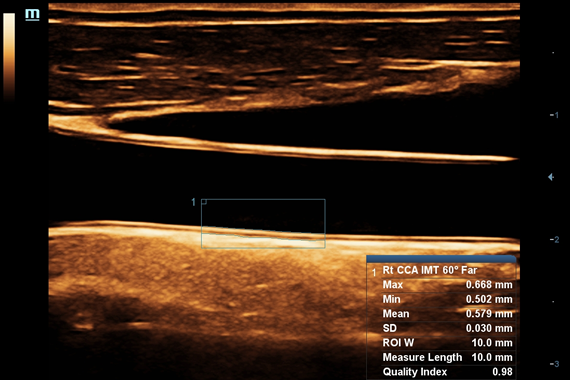

IMT (Intima Media thickness):

Да

• Auto IMT Package – измерения и анализ толщины комплекса интимамедии (КИМ) сонной артерии

Auto IMT+: